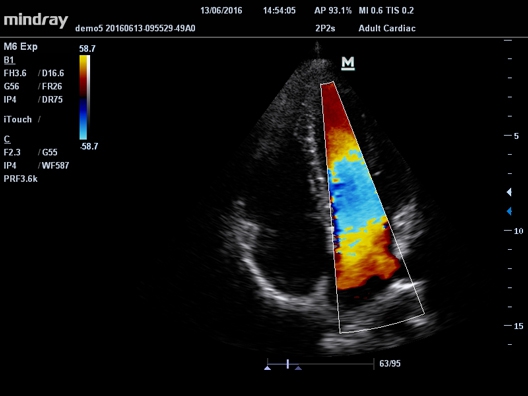

Да

• B/M/Color Dopler/Color M/Power/Directional Power Doppler Flow Imaging

• Cardiac package для кардиологии

• Секторный фазированный датчик Mindray 2P2s